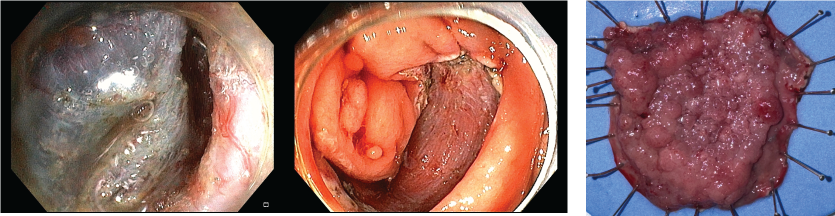

Kết quả bất ngờ: tổn thương được ESD tại manh tràng ổn định, không thấy điểm chảy máu; nguồn xuất huyết thực sự đến từ một polyp lớn chưa xử trí ở đại tràng sigma. Với sự đồng thuận từ người nhà và bệnh nhân, ekip đã tiến hành can thiệp cắt polyp sử dụng endoloop, vừa điều trị vừa giải quyết triệt để nguyên nhân chảy máu.

Kết quả mô bệnh học cho thấy tổn thương là u tuyến ống – nhung mao, có loạn sản độ cao. Đặc biệt, diện cắt đáy và diện cắt bên đều âm tính, tức là không còn tế bào u tại bờ phẫu tích. Điều này khẳng định ca ESD đã cắt trọn tổn thương một cách triệt để, không cần phẫu thuật bổ sung. Như vậy, mặc dù bệnh nhân trải qua nhiều biến cố hậu thủ thuật, nhưng về mặt đánh giá thủ thuật, đây là một ca điều trị thành công, loại bỏ hoàn toàn một tổn thương tiền ung thư có nguy cơ tiến triển.